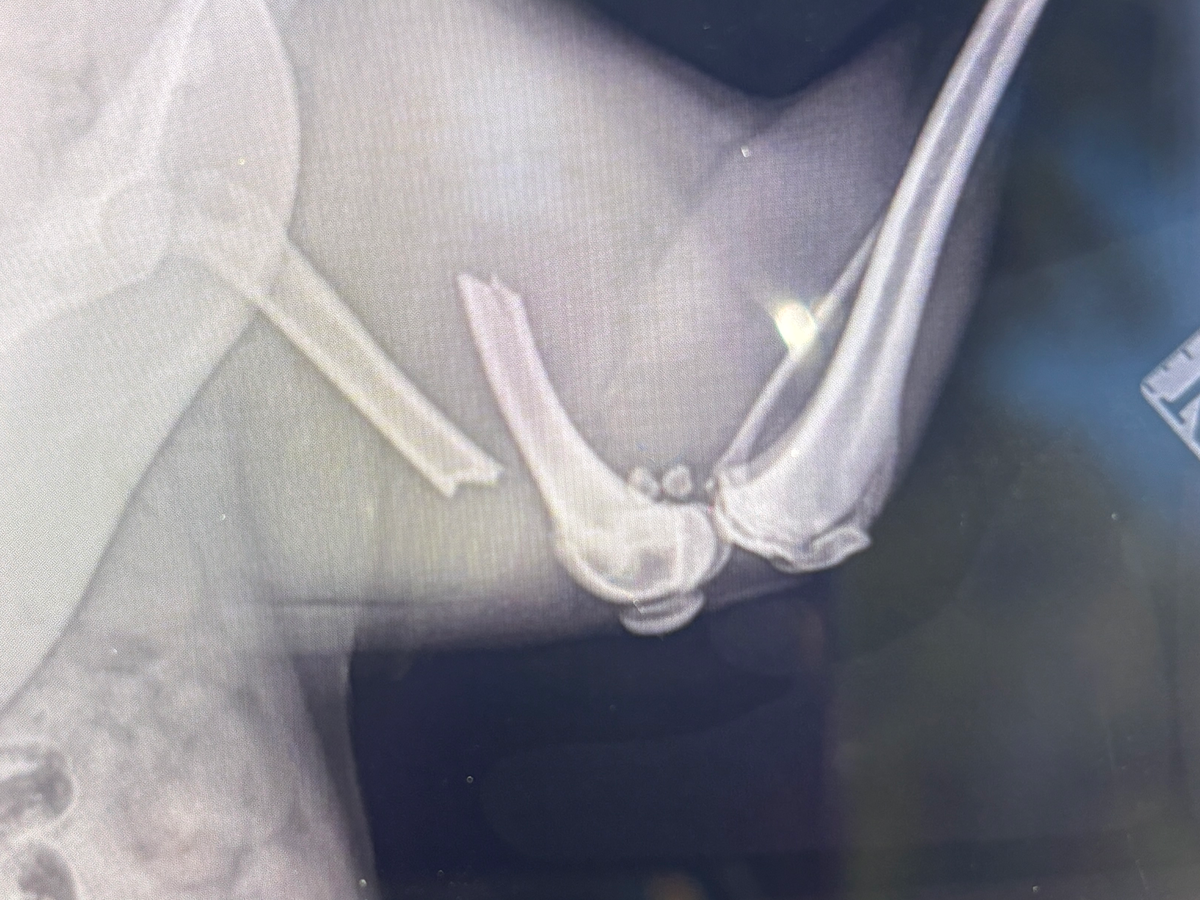

Hi my name is Luna, I broken my FEMA bone on the 23/09/25 and my owner can’t afford the costs to cover the surgery urgently needed.